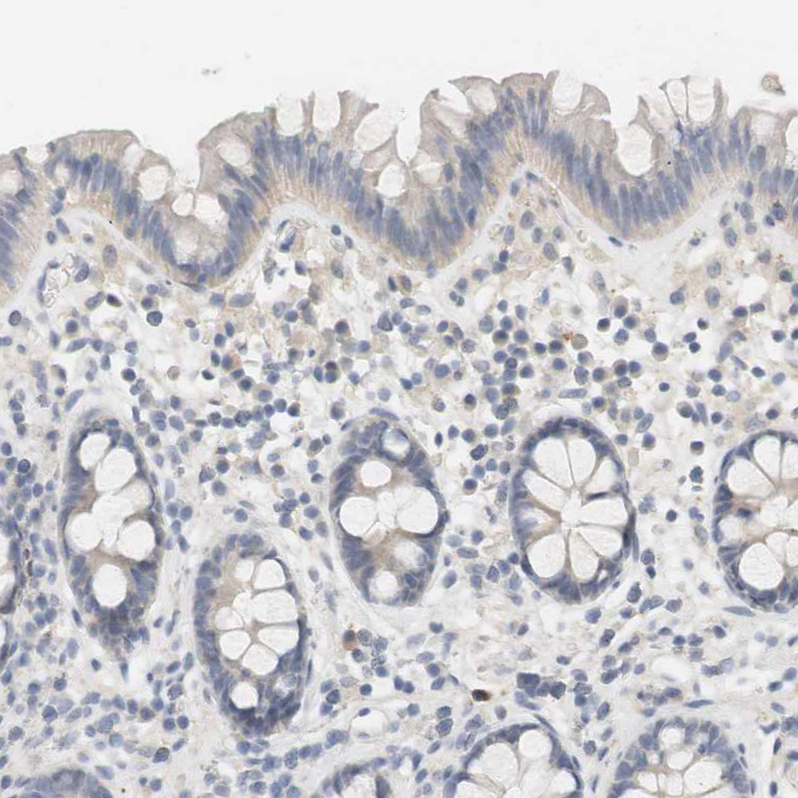

Immunohistochemical staining of human cerebral cortex, colon, liver and lymph node using Anti-RTN3 antibody HPA015650 (A) shows similar protein distribution across tissues to independent antibody HPA015649 (B).